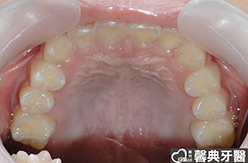

患者︰黃小弟弟,十三歲,學生。

主訴︰戽斗,想做矯正。

治療計劃︰上顎前牙排齊後彈出,下顎前牙排齊後後縮,重建正常咬合關係。